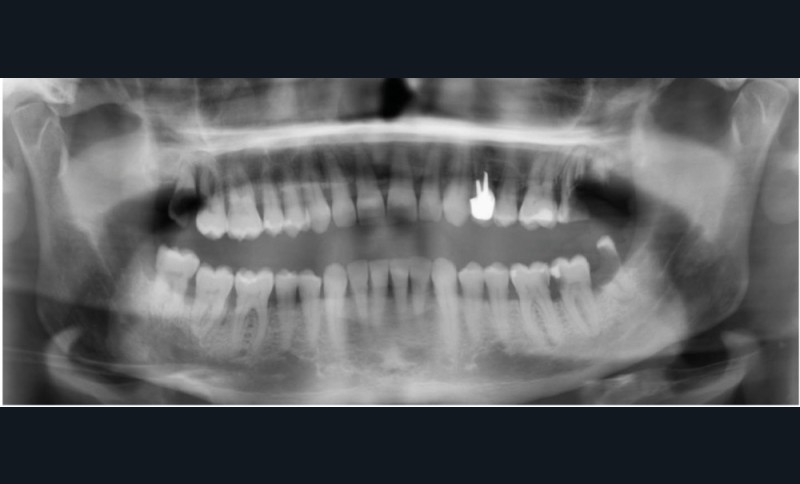

Le principal risque d’ostéonécrose en lien avec une biothérapie est dû à l’inhibiteur du RANKL, le dénosumab (commercialisé sous le nom de Xgeva® en indication oncologique, Prolia® en indication rhumatologique) (fig. 1). Cet anticorps bloque la liaison du RANKL à son récepteur, qui permet notamment l’activation des ostéoclastes. La résorption osseuse est alors bloquée, action intéressante dans le cadre d’une ostéoporose ou de métastases osseuses. Cependant, même si le mécanisme d’action est totalement différent, on retrouve les mêmes effets indésirables que ceux observés avec les bisphosphonates au niveau de la cavité orale. Les patients traités par anti-RANKL présenteront un risque d’ostéonécrose des mâchoires. Ce risque sera évidemment plus ou moins important en fonction de facteurs à rechercher : indication du traitement (oncologique ou rhumatologique), durée totale du traitement, date de dernière administration, corticothérapie associée, diabète, présence de foyers infectieux bucco-dentaires…

Pour les actes invasifs, une suspension de traitement pourra être discutée avec le médecin prescripteur, afin de réduire le risque infectieux au moment de l’acte, mais aussi en postopératoire [1, 2]. La thérapeutique sera reprise lorsque la cicatrisation sera complète. Il est évident que cette suspension de traitement ne doit pas altérer le pronostic de la pathologie et l’état général du patient. En cas d’urgence, les actes nécessaires doivent être entrepris sans délai (fig. 3).